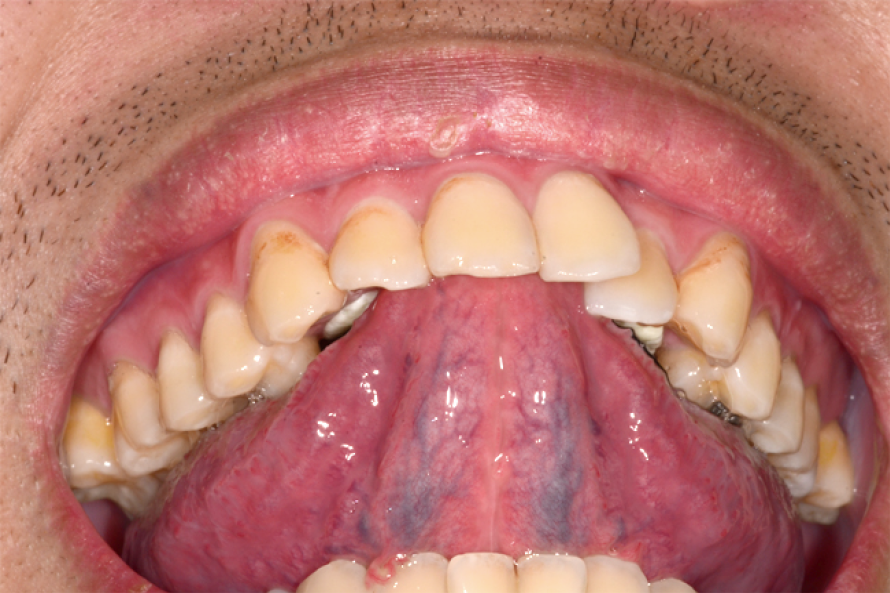

• 再來就是訓練嘴唇,讓雙唇唇緊閉使得時會發出bop-bop的聲音,藉此讓病人訓練用鼻子呼吸。(圖五)